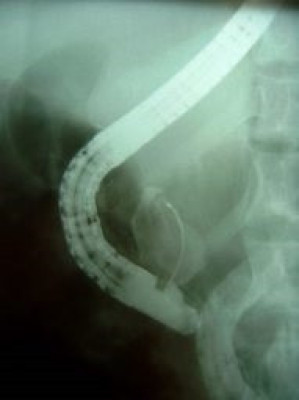

Cálculo gigante y divertículo duodenal ERCP

Envíado por Dr. Carlos Miguel Zavaleta Consuegra